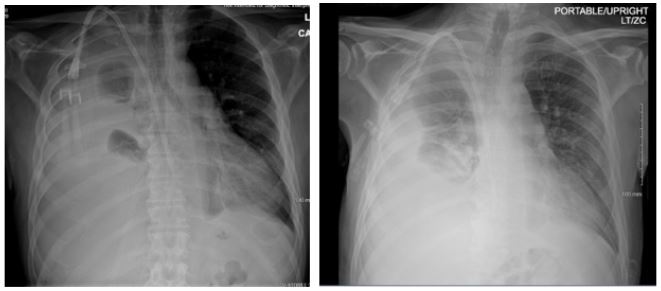

Patient presented with elevated blood pressure at 174/88. BMP was significant for Na 133, K 4.6, BUN 29, Cr 5.3. CMP is significant for Albumin 2.5. CBC was significant for Hb 8.7, Hct 25.0. D-dimer was found elevated at 4,670. PT and INR were normal. ABG significant for pH 7.52, pCO2 31.4, HCO3 25.3. A chest x-ray on admission demonstrated a large right-sided pleural effusion, contributing to significant compressive atelectasis of the right lung and leftward deviation of the mediastinal structures. Thoracentesis was performed, which demonstrated blood- tinged serosanguinous fluid. Transthoracic echocardiogram demonstrated EF 60-65%, LV diastolic dysfunction, with trace mitral and tricuspid regurgitation, and was negative for pericardial effusion. CT Chest demonstrated a large volume right-sided pleural effusion without pneumothorax, with extensive progressive atelectasis throughout the right lung. There was also a trace left-sided pleural effusion and pleural thickening with round atelectasis in the posterior left lower lobe, as well as minimal interstitial edema in the left lung. A chest tube was placed with consistent drainage throughout admission. Repeat chest x-rays continued to demonstrate pleural effusion. Thoracotomy, decortication, and pleurodesis were performed with Video-Assisted Thoracoscopic Surgery (VATS), with significant improvement of symptoms. The pleural fluid biopsy was negative for malignancy and revealed fibrocollagenous tissue with chronic inflammation and a few reactive epithelial cells. Thorough review of the patient’s medication list led to suspicion that the patient’s 50 mg Hydralazine three times a day may be the offending agent. Anti-histone antibody titers were found to be elevated at 3.7. Free Kappa and Lambda light chains were elevated. Antinuclear Antibody (ANA) titers were found to be negative. Hydralazine was discontinued, and after chest tube removal and improved chest x-ray, the patient was discharged home. It was recommended that the patient follow up with their primary care provider and rheumatologist.

Figure 2: Axial and coronal view of chest CT with IV contrast demonstrating large right sided pleural effusion with compressive atelectasis.